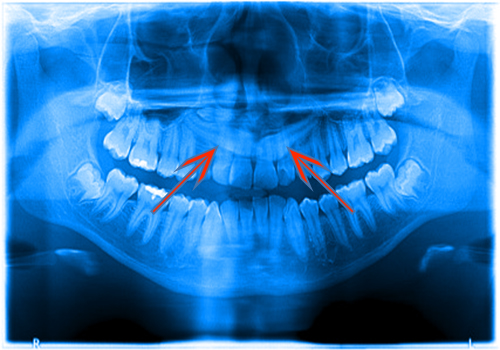

Köpek dişleri ön dişler arasında en geç sürendir. Yaklaşık 13 yaşına kadar ağızdaki yerini alır.Kimi durumda çeşitli nedenlerle süremez gömülü olarak kalır. Akıl dişlerinden sonra sıklıkla gömülü kalan dişler köpek dişleridir. Süremeyen bu dişler genellikle damak tarafında ; seyrek olarak da dudak tarafına daha yakın olarak gömülü kalmaktadırlar.

Hastanın yaşı ilerledikçe; gömülü olan köpek dişinin sürme olasılığı zayıflar. Eğer diş dizisindeki yerini zamanında alamamışsa ;sürmesini engelleyen sebebin ne olduğu araştırılmalıdır. Bazen dişler sıkıştırır ve yeterli alan yoktur. Bazen kalın diş etleri yada kemik dokusu dişin ilerlemesine engel olmuştur. Çoğu zamanda “süt dişleri “ erimeyip erişkin yaşlarda yerinde kalır ve “sürekli diş” kemik içinde kalmıştır.